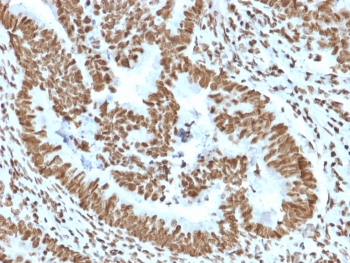

ZNF846 Zinc Finger Transcription Regulator Antibody Colon Carcinoma IHC. Immunohistochemistry analysis of FFPE human colon carcinoma tissue using ZNF846 Antibody (clone PCRP-ZNF846-1E12) shows strong nuclear staining in tumor epithelial cells, consistent with ZNF846 localization as a zinc finger transcription-associated protein. The staining highlights glandular tumor structures with prominent nuclear signal, while surrounding stromal regions display comparatively lower staining intensity. Hematoxylin counterstain provides nuclear contrast and tissue architecture. HIER: boil FFPE tissue sections in pH 9 10 mM Tris with 1 mM EDTA for 20 min and allow to cool before testing.